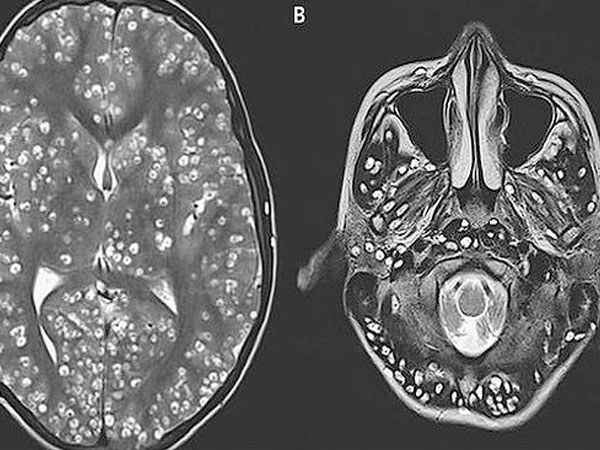

Một trường hợp đáng ngại vừa được đăng trên Tạp chí y học New England, đó là việc một thiếu niên thiệt mạng do quá nhiều trứng sán xơ mít trong não. Trước đó, nam thanh niên 18 tuổi ở Ấn Độ được đưa đi cấp cứu tại bệnh viện trong tình trạng bất tỉnh sau cơn động kinh. Các bác sỹ phát hiện trong não của thiếu niên có quá nhiều trứng sán làm tổ trong vỏ não. Đây là nguyên nhân, gây ra tình trạng co giật. Bệnh nhân đã được điều trị bằng thuốc chống viêm và thuốc chống động kinh. Tuy nhiên sau hai tuần điều trị, bệnh nhân vẫn không qua khỏi.

Các bác sỹ sẽ chỉ định các xét nghiệm để xác định chính xác. Xét nghiệm phân và soi tươi dưới kính hiển vi tìm trứng sán. Chụp CT scanner não, chụp MRI khi có chỉ định can thiệp kỹ thuật vì cần độ chính xác cao, soi đáy mắt tìm hình ảnh và vị trí nang sán…